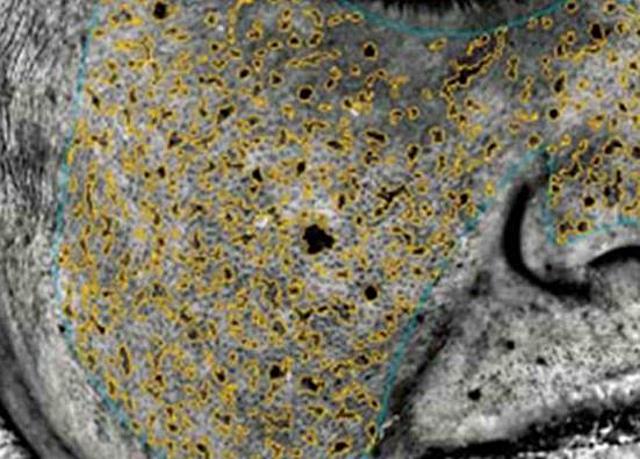

【テスト1:潜在シミへの効果】

専門機器で効果を測定し、まだ肌の表面に出ていない潜在シミを計測。モニターの数値を平均し、マイナスの値が大きいほど「効果アリ」と評価しました。